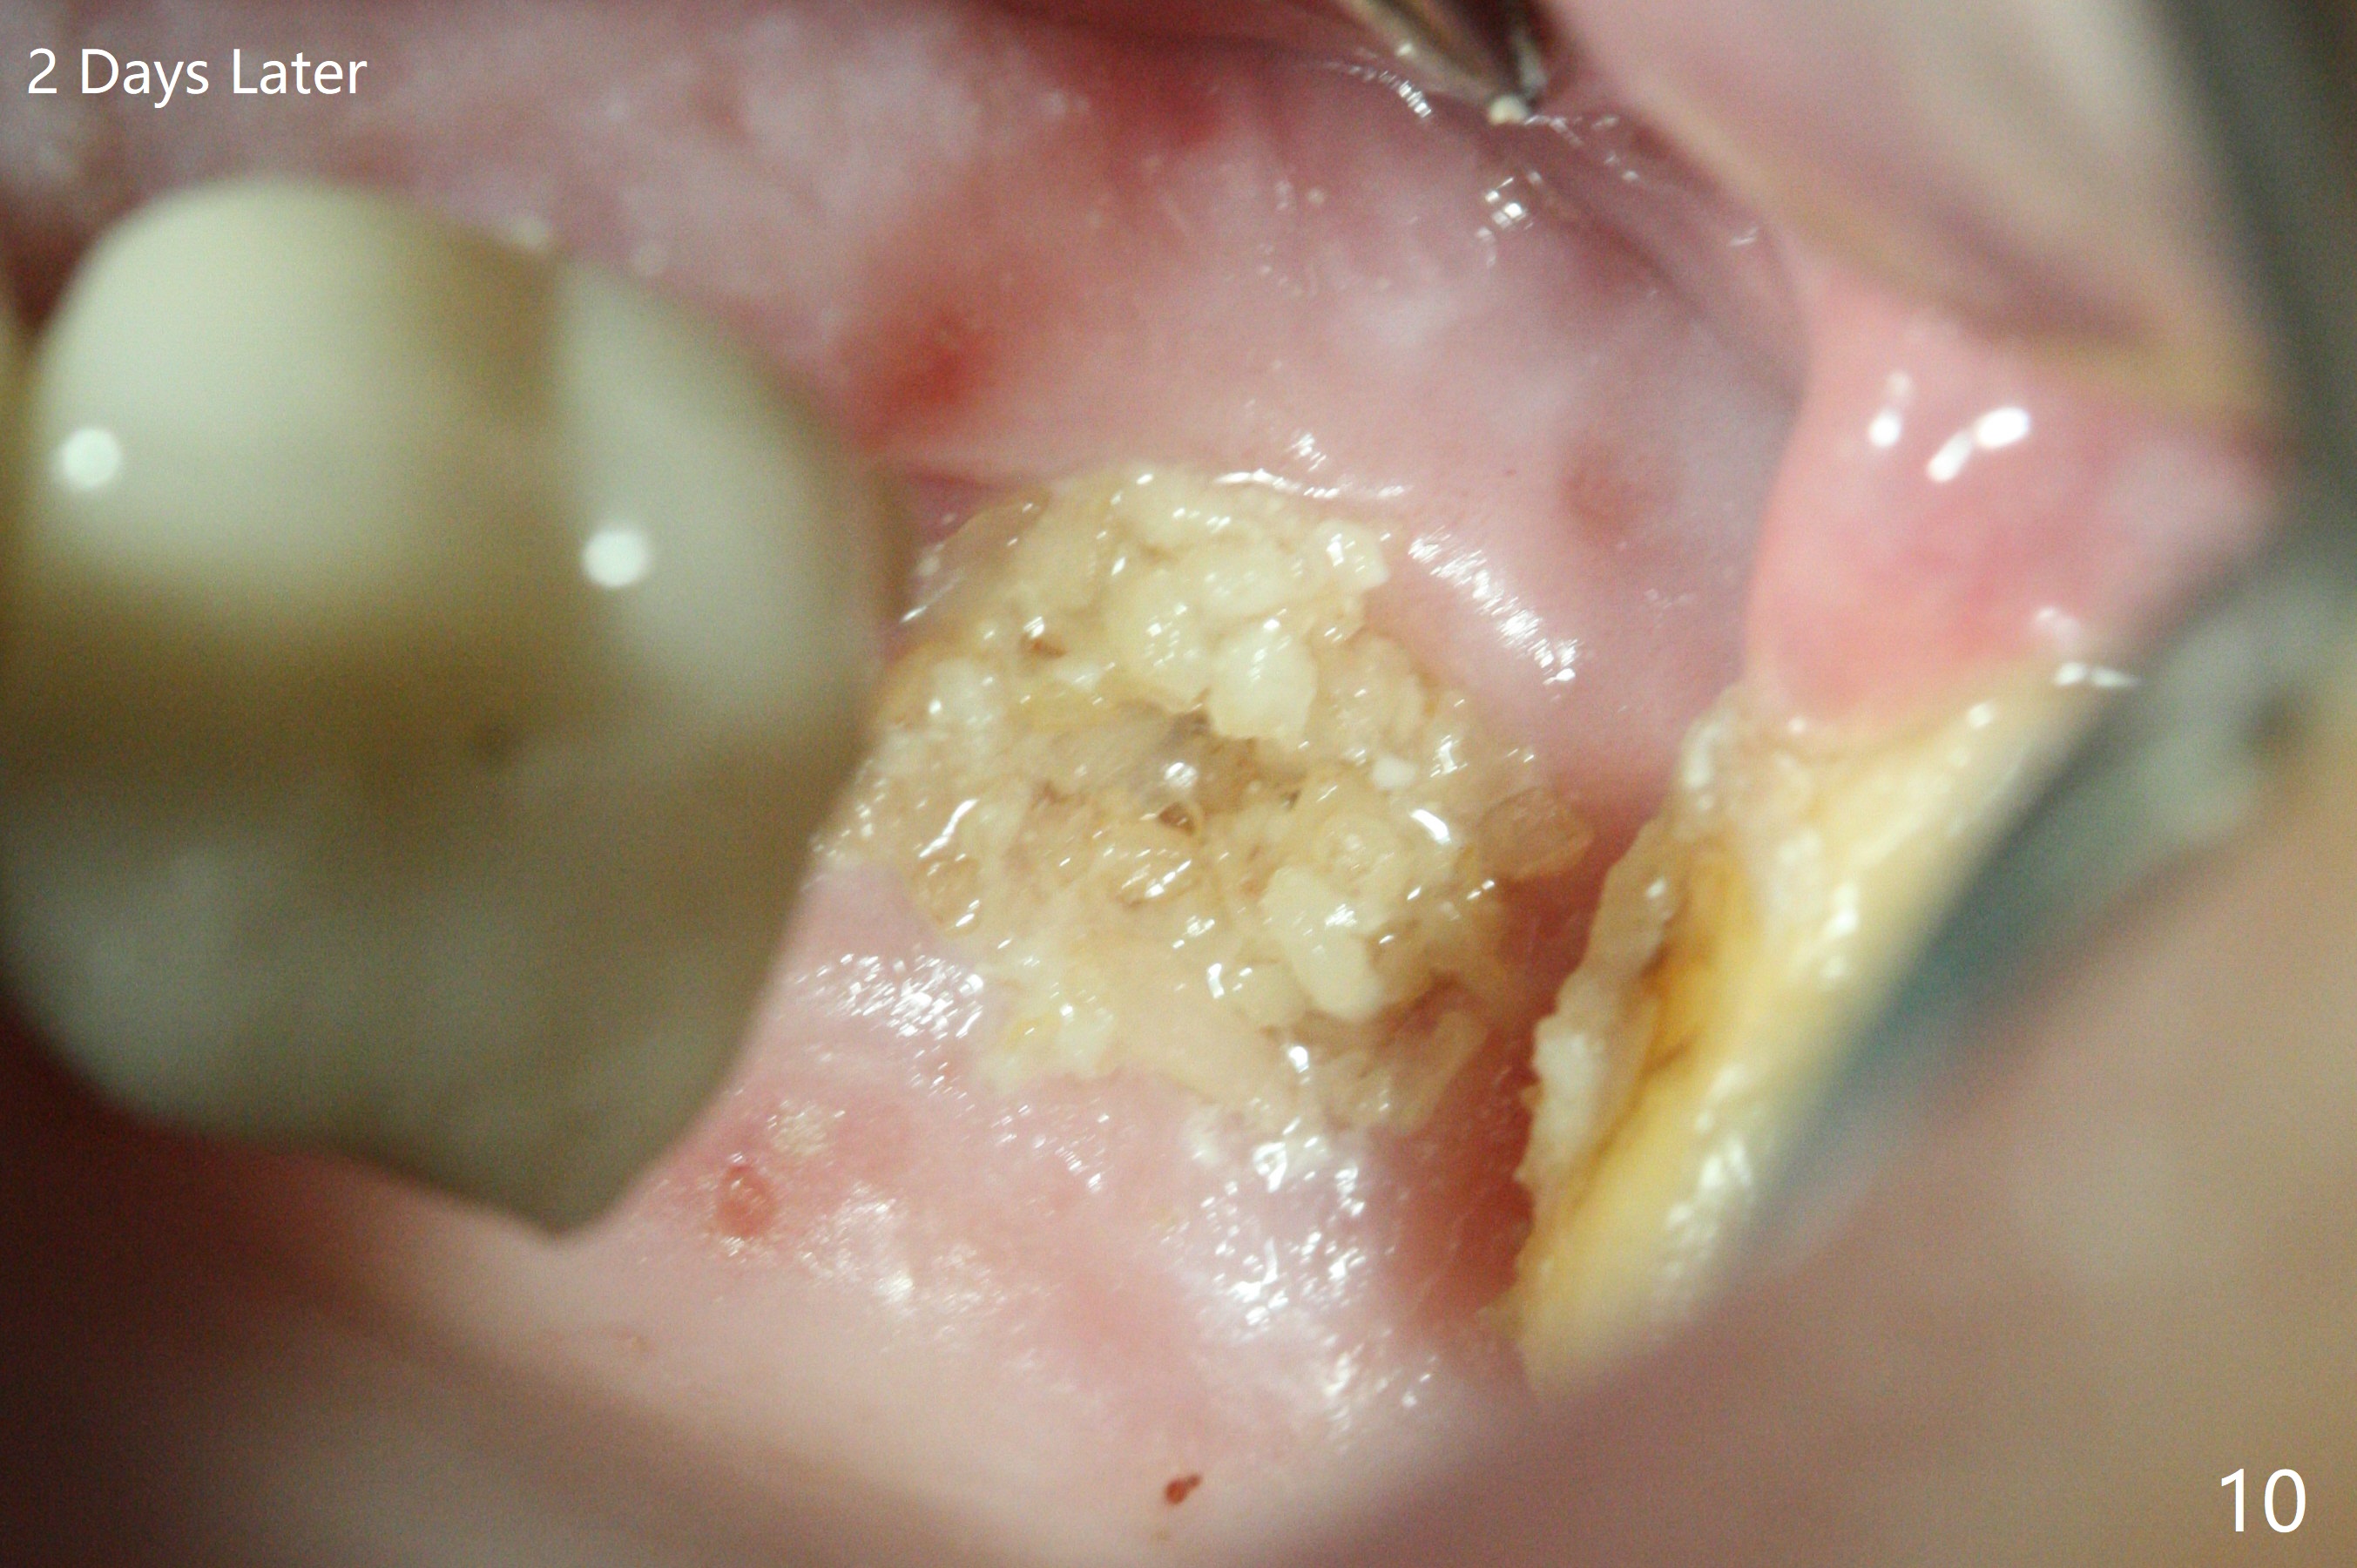

The 7x14 mm implant at #15 of a 89-year-old man is found to be loose ~ 1 year post cementation (Fig.1). After implant removal and debridement, bone graft is placed (Fig.2 G); the mesiocervical caries of the 3rd molar is removed, but not filled (*). With collagen membrane fixed with Chromic gut suture (Fig.3), setting acrylic is applied in the edentulous area, including the mesiocervical cavitation of the 3rd molar (Fig.4) for further retention. Bone graft gets lost following socket preservation at #31 with periodontal dressing. When the bone graft matures, a new implant (Fig.6 green) will get primary stability from the native bone, i.e., coronal to the sinus floor (Fig.5 F). The acrylic dressing (Fig.7 A) with a portion locking to the undercut of the neighboring crown (*) remains in place 5 weeks postop. When the dressing is cut off, the bone graft is exposed with odor (Fig.8,9 *). Periodontal dressing is applied. The distolingual portion of it gets lost due to brushing a day later. When he returns, the dressing is removed (Fig.10). It appears that the growing in gingival margin is pushing the bone graft out. A moment later after just a few rounds of swallowing, more graft is lost (Fig.11). We would love to leave the wound open, but the senior citizen complains of air leaking and requests reapplication of periodontal dressing. The bone graft is almost gone when the 2nd periodontal dressing is removed nearly 2 months postop (Fig.12). The tooth sensitivity disappears when MO caries is taken care of. The socket has a dimple 5 months postop (Fig.13), although it is filled with bone graft (Fig.14). Due to low bone density (~500 HU), sinus lift is required for implant stability with PRF (Fig.15). In fact the lab chooses not to do sinus lift.